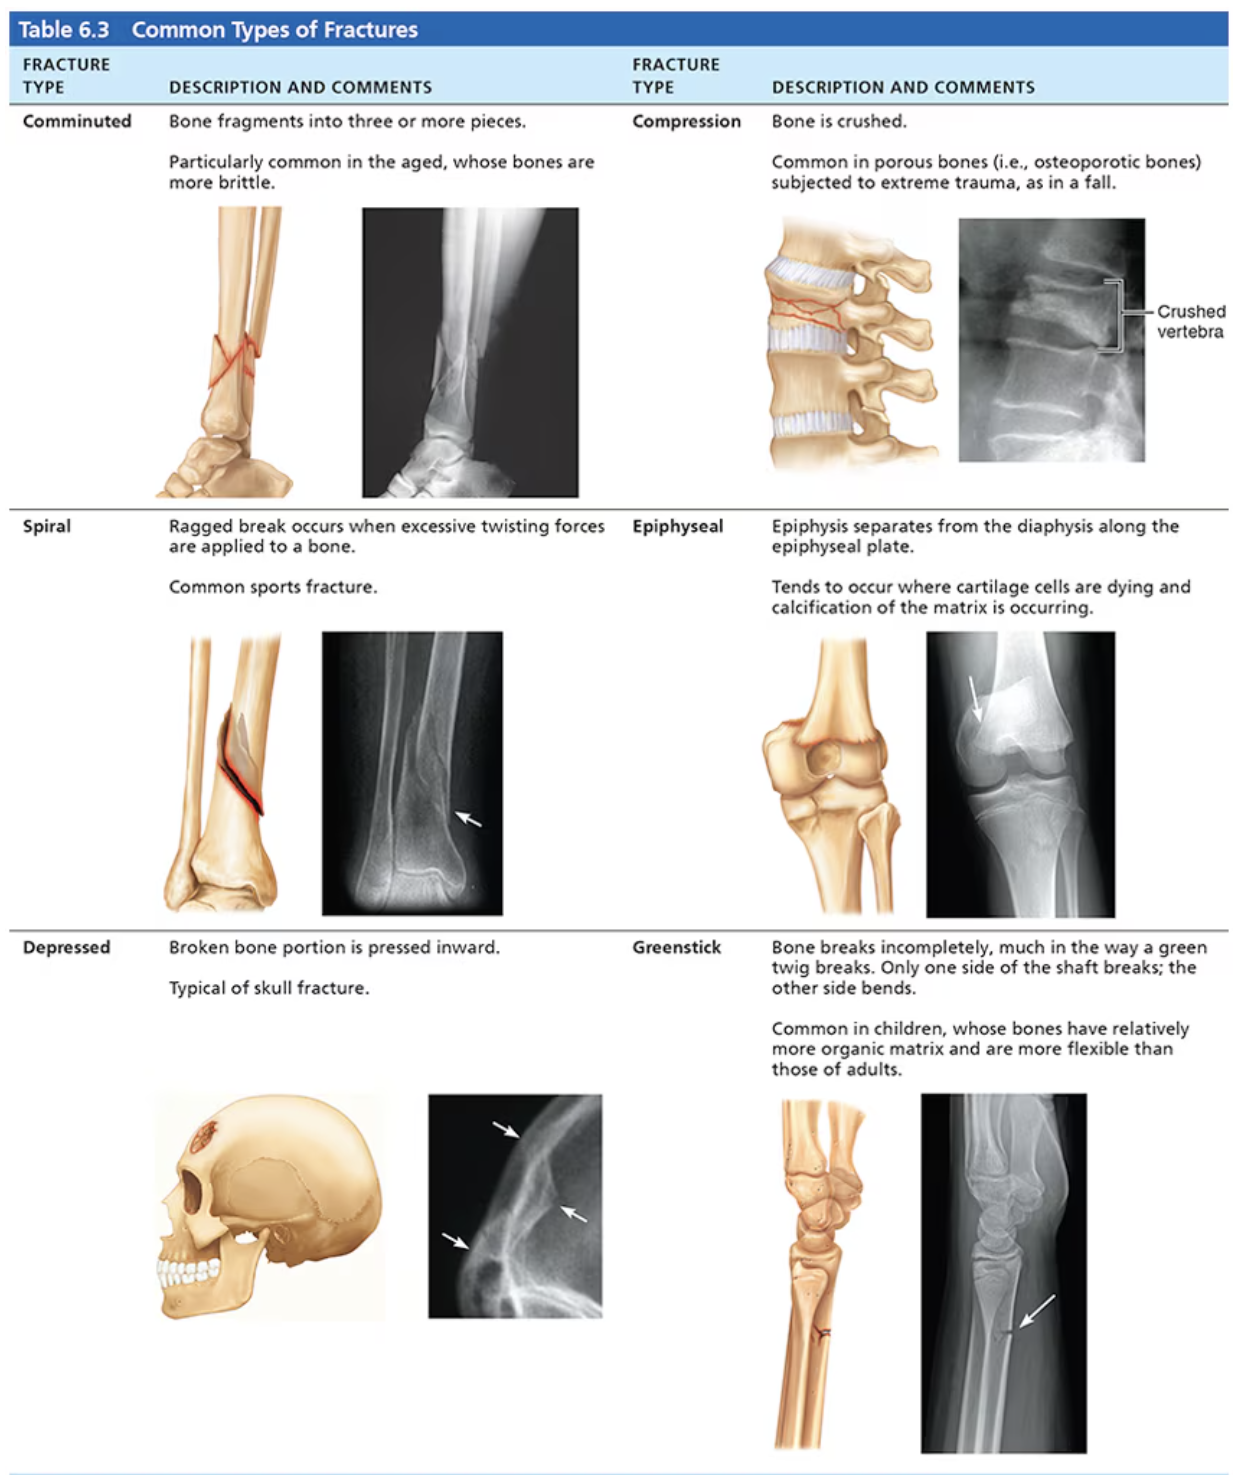

Fracture classification:

Position of bone ends after fracture.

Nondisplaced: ends retain normal position.

Displaced: ends put of normal alignment.

Completeness of break.

Complete: broken all the way through.

Incomplete: not broken all the way through.

Whether skin is penetrated

Open(compound) - skin is penetrated.

Closed(simple) - skin is not penetrated.

Comminuted : bone fragments into three or more pieces. Aged people since bones are more brittle.

Compression: bone is crushed, often porous bones or bones subjected to extreme trauma.

Spiral: ragged break occurs when excessive twisting forces are applied to a bone.

Epiphyseal: epiphysis separates from the diaphysis along the epiphyseal bone.

Depressed: broken bone portion is presses inward. Typical of skull fracture.

Greenstick: bone breaks incompletely, much in the way a green twig breaks. Only one side of the shaft breaks; the other side bends. Common in children.